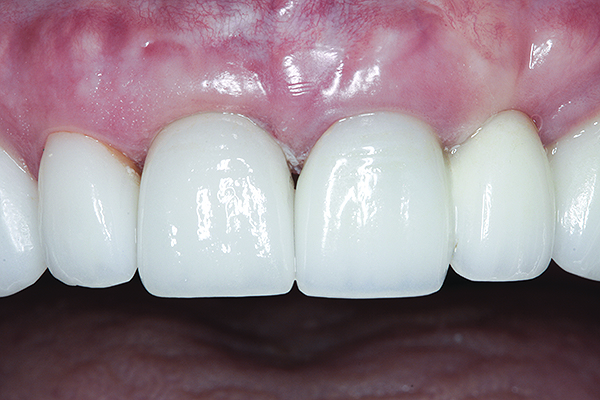

The crown was inserted and secured with a luting composite (Multilink® Automix, Ivoclar Vivadent) (Figure 17); a radiograph confirmed complete removal of excess cement (Figure 18). At the 4-month follow-up appointment, the soft tissues were healed within normal limits, and the patient was pleased with the esthetic outcome of the definitive restoration (Figure 19 and Figure 20).

Fig 19 and Fig 20. Four-month follow-up appointment. The soft tissues had healed within normal limits (Fig 19), and the patient was pleased with the esthetic outcome of the definitive restoration (Fig 20).